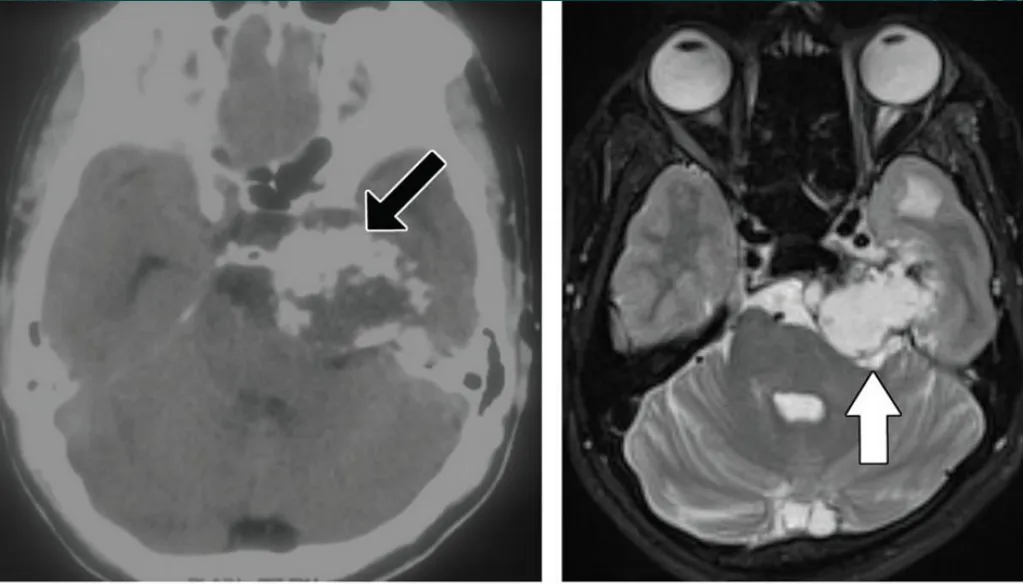

典型病例影像学表现

软骨肉瘤伴岩尖区膨胀性骨质破坏,侵犯左侧海绵窦后部

海绵窦黑色素瘤,需与海绵状血管瘤进行鉴别诊断